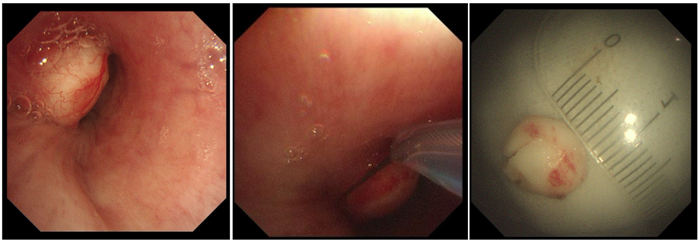

患者左主支氣管遠(yuǎn)端見結(jié)節(jié)狀白色腫物,表面上有少許表淺血管顯露,基底較寬,堵塞管腔約70%,予以高頻電套扎切除,少許出血,給與局部噴灑腎上腺素溶液止血,標(biāo)本送病理。2月16日病理結(jié)果示:肺錯構(gòu)瘤?;颊哂?月16日出院,醫(yī)護(hù)人員就復(fù)診問題給予其詳細(xì)的指導(dǎo)。

2月15日,由于世倫副院長親自操作,在狄紅紅主治醫(yī)師、田忠敏護(hù)士長協(xié)助下,成功為患者行高頻電套扎切除結(jié)節(jié)狀白色腫物。